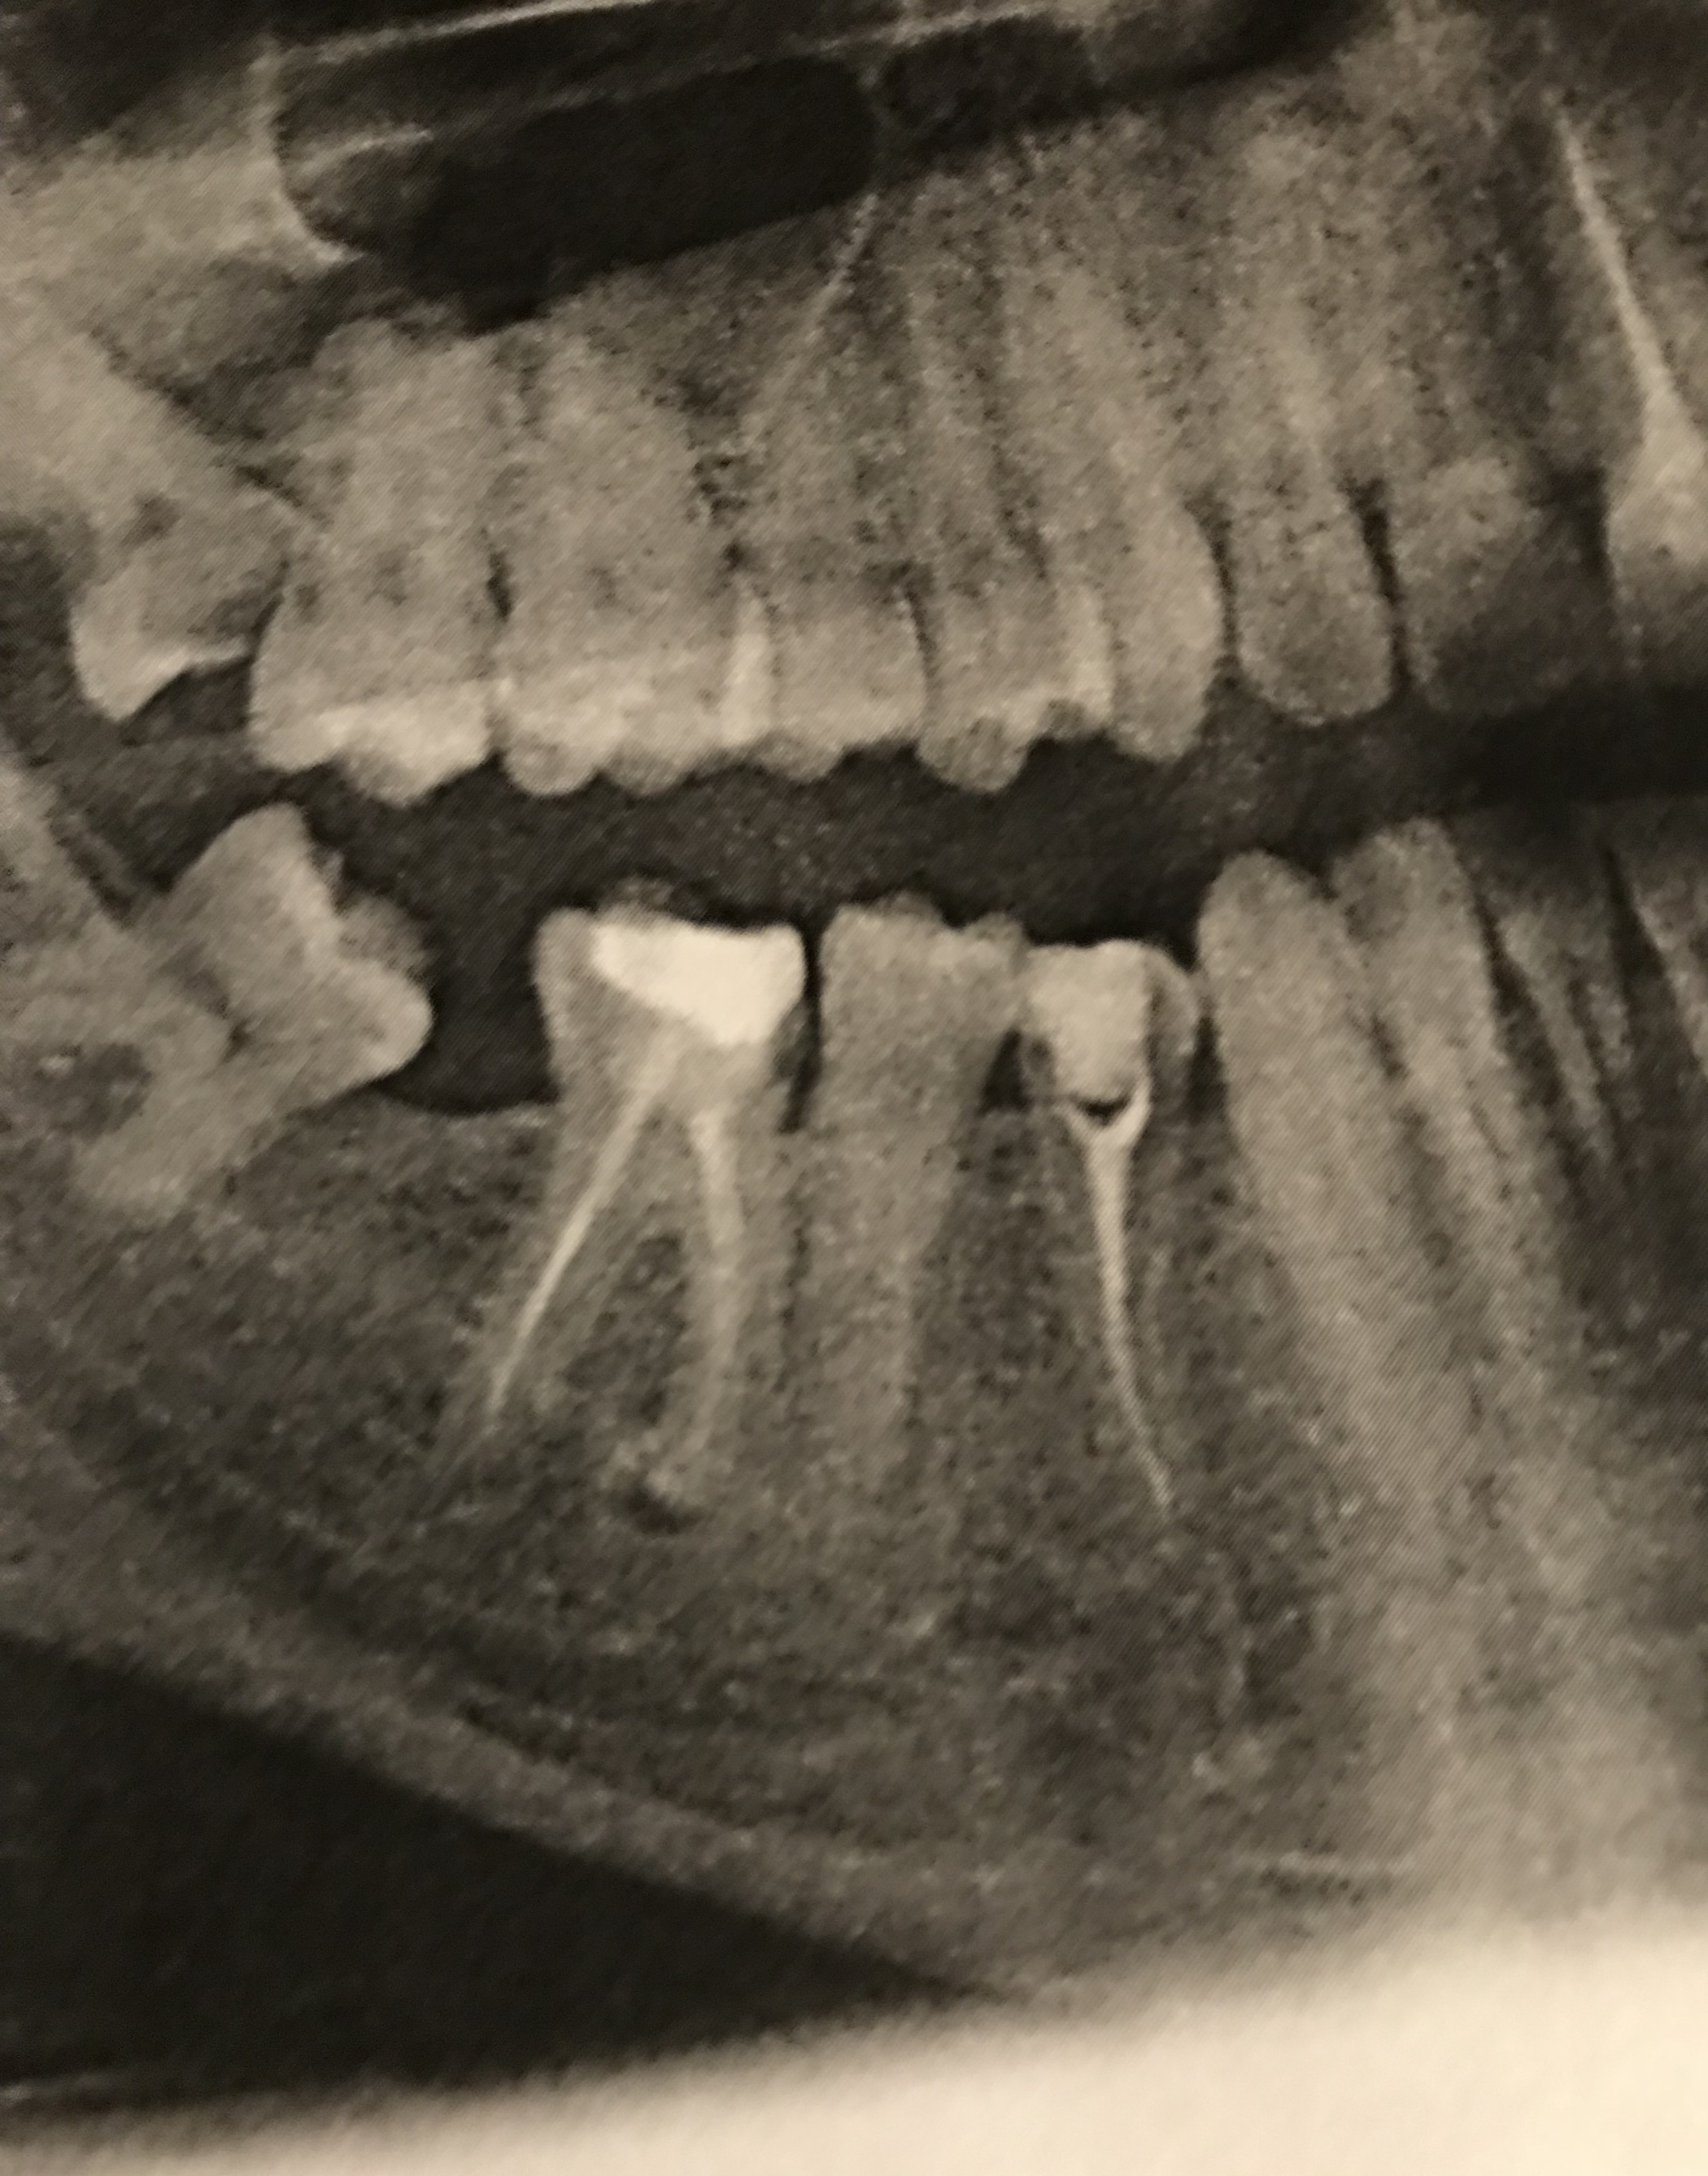

Рентгеновские снимки кариеса корня зуба

Раздел: Визуальные уроки